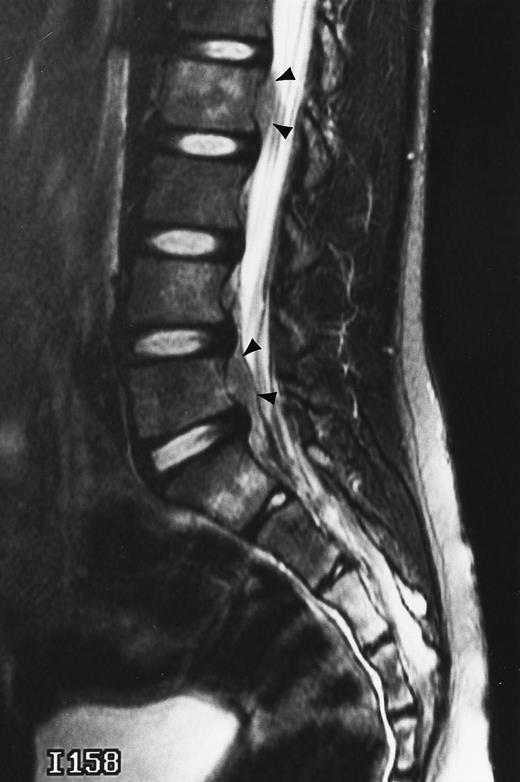

Normal appearance of spinal bone marrow in a 45-year-old woman: T1-weighted (500/11, TR/TE) (A) and T2-weighted, fat-suppressed fast spin echo (4000/96, TR/TE, ET 16) (B) sagittal MR images of the lumbar spine. Note increased signal of the vertebral bodies, relative to the intervertebral discs in (A) and increased deposition of fatty marrow around the basivertebral veins (arrowheads). On the T2-weighted image, normal intervertebral discs are brighter than the vertebral bodies; low signal in the L4-L5 and L5-S1 discs is due to degenerative changes (arrows).